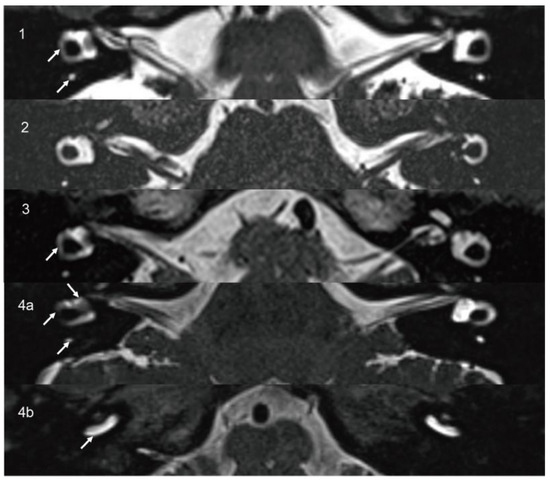

3.1.4. Case 4

| 4 | 45 | F | Tinnitus, HL, recurrent vertigo | Right 4.3 mm | Intravestibular | 48 | LFHL | NP | CP = 100% right side hypofunction | Absent on unaffected side | Absent on both sides |